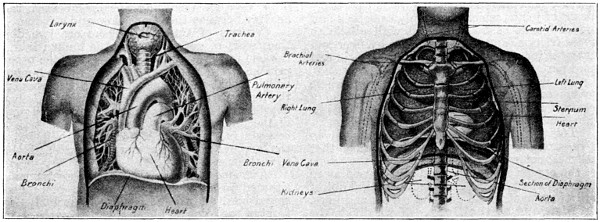

ITS STRUCTURE—ORGANIZATION INTO SYSTEMS—FUNCTIONS—SPECIAL SENSES—NERVOUS SYSTEM—PERSONAL HYGIENE—PREVENTION OF DISEASE—INTERDEPENDENCE OF BODY AND MIND—EUGENICS—ILLUSTRATIONS AND CHARTS.